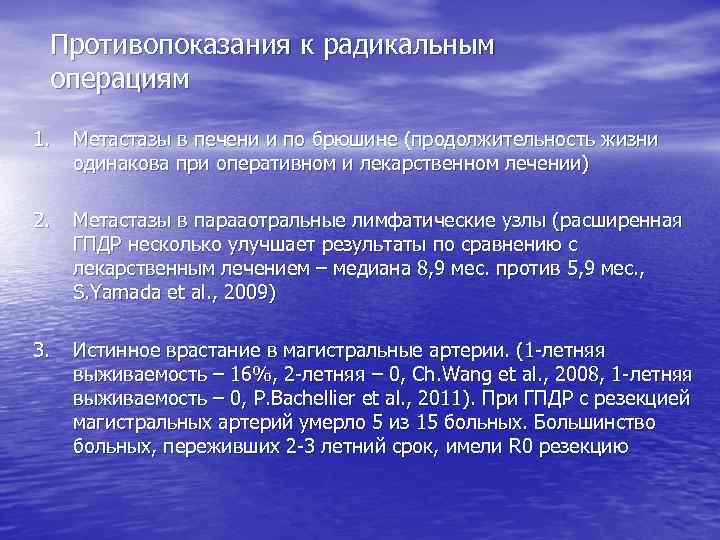

Противопоказания к радикальным операциям 1. Метастазы в печени и по брюшине (продолжительность жизни одинакова при оперативном и лекарственном лечении) 2. Метастазы в парааотральные лимфатические узлы (расширенная ГПДР несколько улучшает результаты по сравнению с лекарственным лечением – медиана 8, 9 мес. против 5, 9 мес. , S. Yamada et al. , 2009) 3. Истинное врастание в магистральные артерии. (1 -летняя выживаемость – 16%, 2 -летняя – 0, Ch. Wang et al. , 2008, 1 -летняя выживаемость – 0, P. Bachellier et al. , 2011). При ГПДР с резекцией магистральных артерий умерло 5 из 15 больных. Большинство больных, переживших 2 -3 летний срок, имели R 0 резекцию